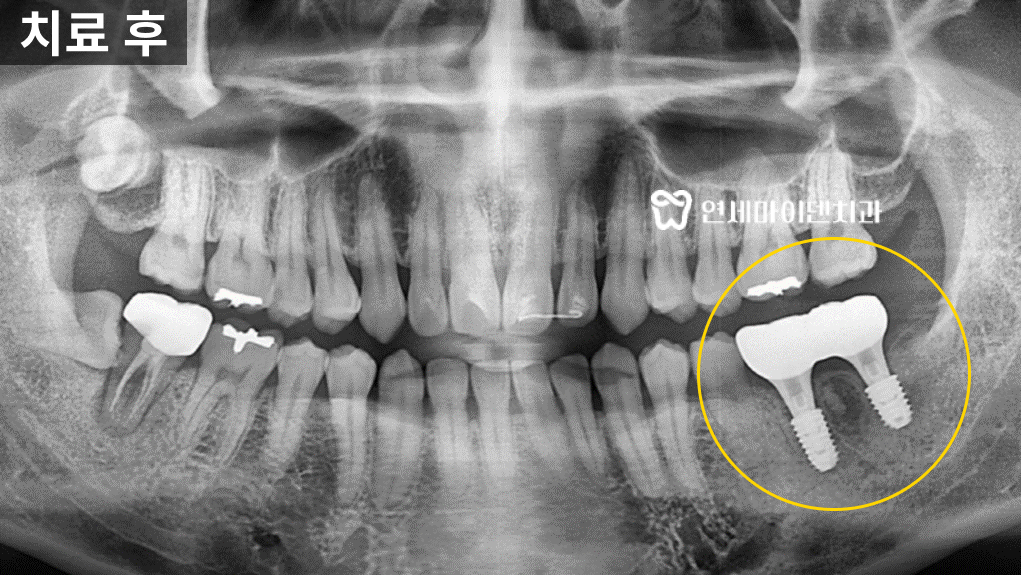

지체없이 발치한 후 임플란트를 진행하기로 했습니다.당일 수술이 결정되었지만, 3D 네비게이션 정밀 진단을 통해

당일 발치 즉시 임플란트를 진행하였습니다.환자분께서는 당일 바로 발치와 임플란트를 식립하는 것에 걱정이 있으셨지만,

첨단 장비를 통해 환자분의 치아와 잇몸 상태가 철저히 분석돼고

여러번의 모의 수술 후 수술이 진행되는 것을 확인하시고는

안심하시고 수술을 받기로 결정하셨습니다.발치 즉시 임플란트 준비 과정

임플란트 수술을 진행하기 위해서

먼저 엑스레이와 CT 촬영을 진행합니다.검사를 통해 신경관의 위치와 치아 주변 뼈 상태를

꼼꼼하게 확인합니다.특히, 아래턱에 임플란트를 식립할 때에는

신경관이 지나가는 경로를 꼭 정확하게 파악해야 합니다.

만약 임플란트를 하치조 신경관에 너무 가깝게 심는다면

신경 손상이 발생할 수 있기 때문입니다.신경 손상이 발생하면 입술이나 턱 주변이 마비되거나

심한 통증을 느낄수 있어서 매우 섬세한 작업이 필요합니다.이 환자분의 경우에도 CT 촬영을 통해 신경관의 위치를 정확하게 파악했고

이를 토대로 임플란트를 안전하게 심을 수 있는 위치와

정확한 각도를 설정해주었습니다.임플란트 수술 전 치과의사의 준비 루틴

치아와 뼈가 재생되지 않고 염증이 점점 심해져 주변치아의 예후까지 위협할 수 있습니다.따라서 해당 치아는 발치 즉시 임플란트를 진행하기로 하였습니다.

임플란트 식립 시에는 임플란트를 식립할 위치와 각도가 매우 중요합니다.

수술 전 환자분과 상의 후 3D 네비게이션으로 모의 수술을 통해

임플란트를 식립할 위치를 정확히 설정했습니다.또, 발치 직후에는 기존에 있던 염증들을 깨끗하게 제거해야만

미세현미경을 통한 염증의 제거와 3D 네비게이션을 활용하여

발치 즉시 임플란트 식립을 진행하였습니다.식립 이후 잇몸 뼈가 잘 회복되는 것을 확인한 뒤

2차 임플란트 수술 후 최종 보철물까지 올려 치료를 마무리 했습니다.임플란트 수술 전, 고려해봐야 하는 것들